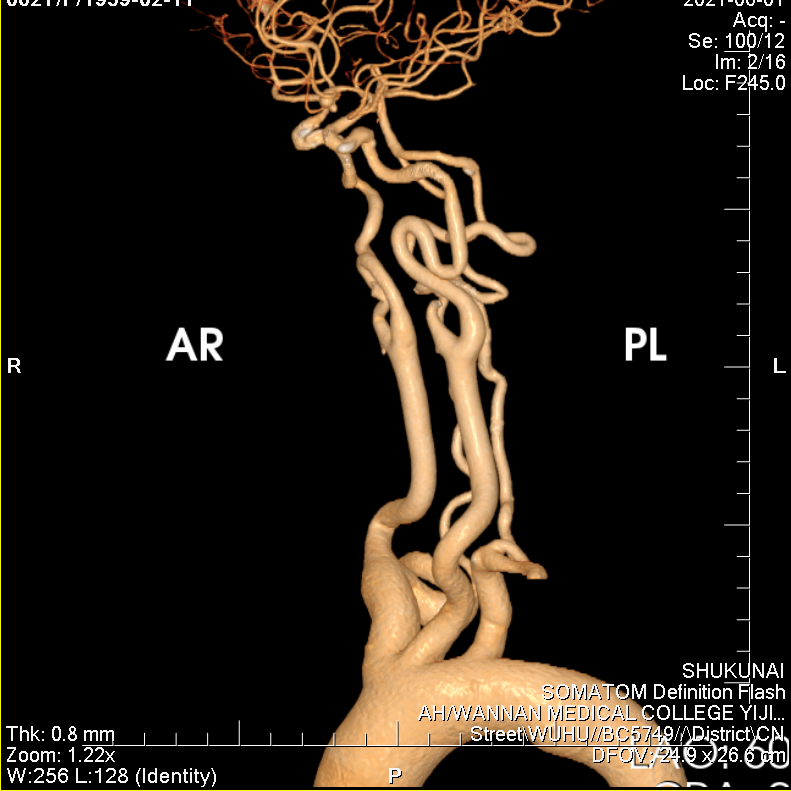

左侧颈内动脉极度迂曲。

70cm长鞘置于左侧颈内动脉近端,用泥鳅导丝将通桥银蛇®DA远端通路导引导管带过第一个弯。

用Plus导管将通桥银蛇®DA远端通路导引导管带至海绵窦段。